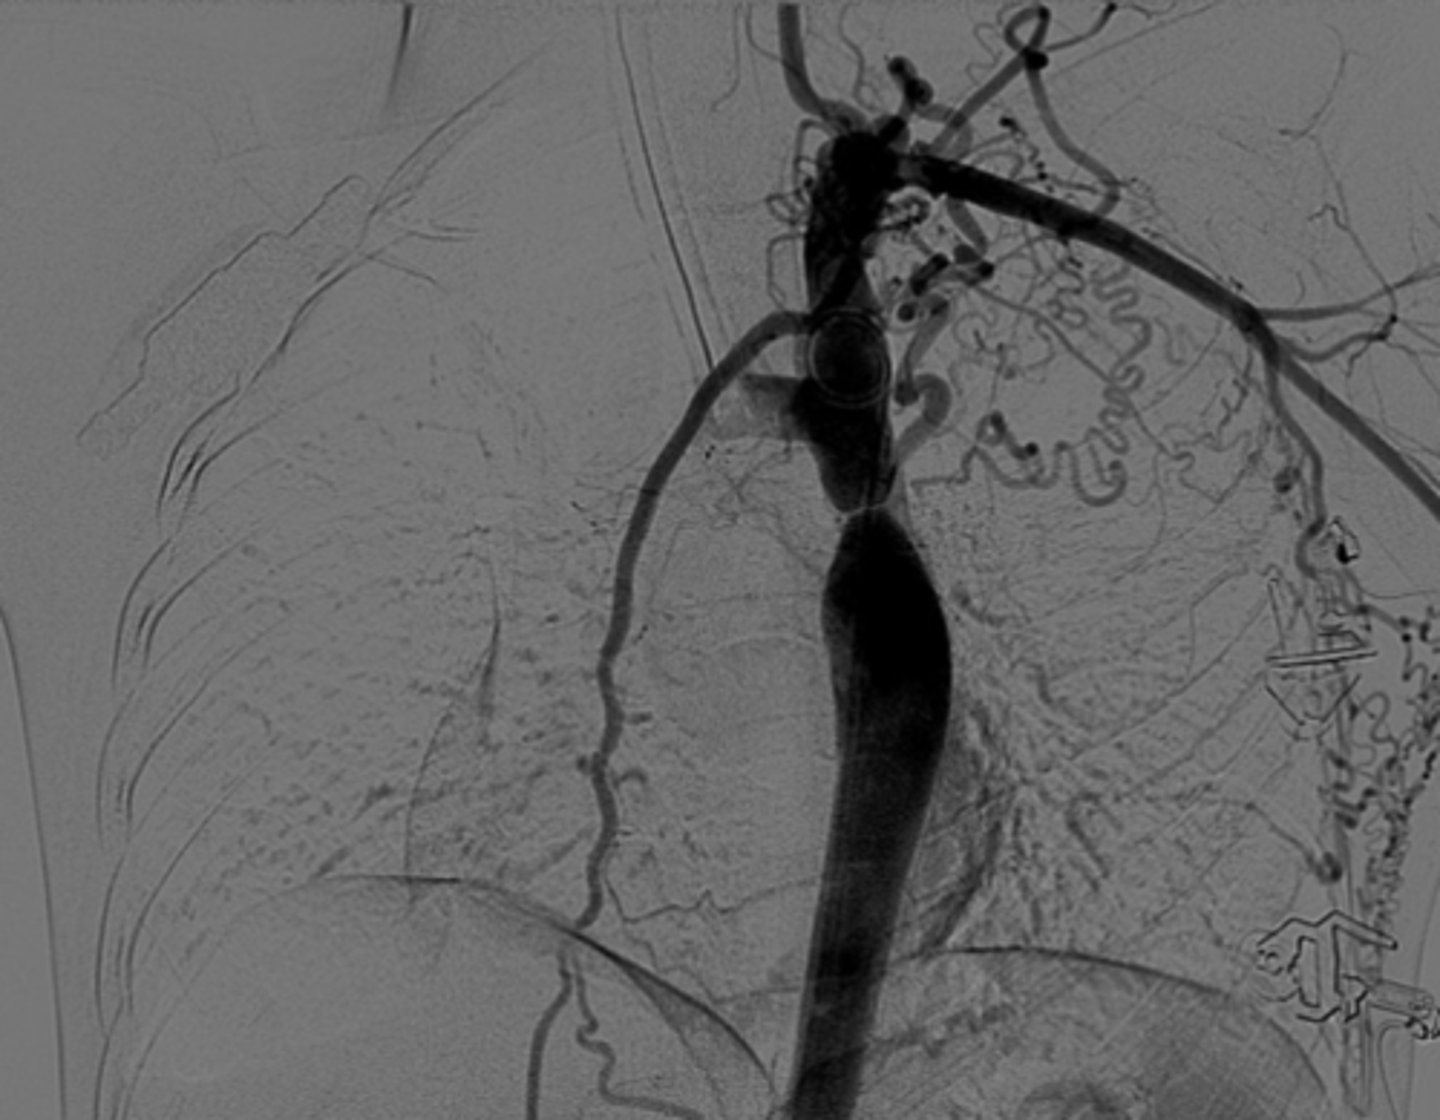

Know the development of the aortic arches figure

knowt flashcard image